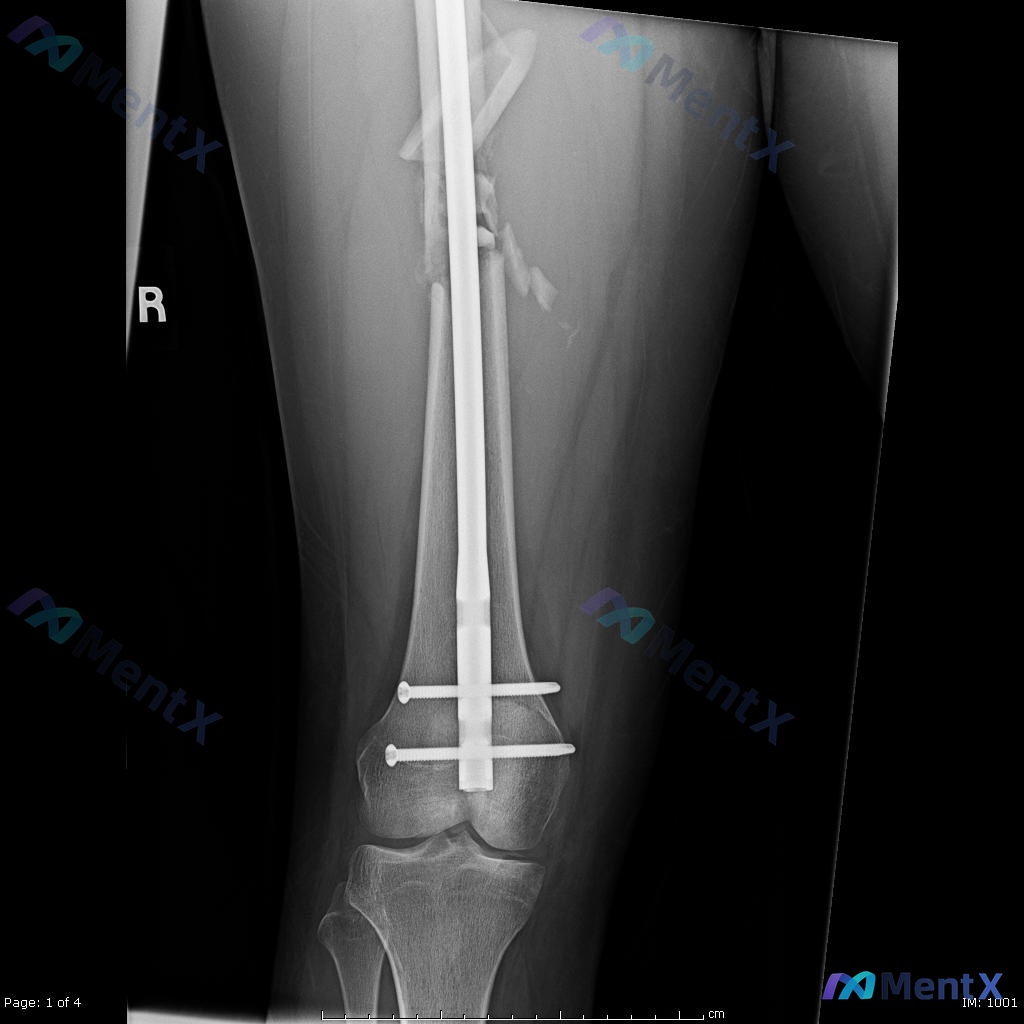

看到一个挺有代表性的创伤骨科病例,结合影像和临床分析整理了一下思路,关于「髓内钉固定术后负重时机」的误区其实还挺普遍的。 --- 一、先把病例核心信息捋清楚 基本情况:22岁男性,高能量车祸受伤 影像关键所见: - 术前(图A/B):右侧股骨干中段粉碎性骨折,多块游离骨块,移位明显;局部软组织肿胀;...